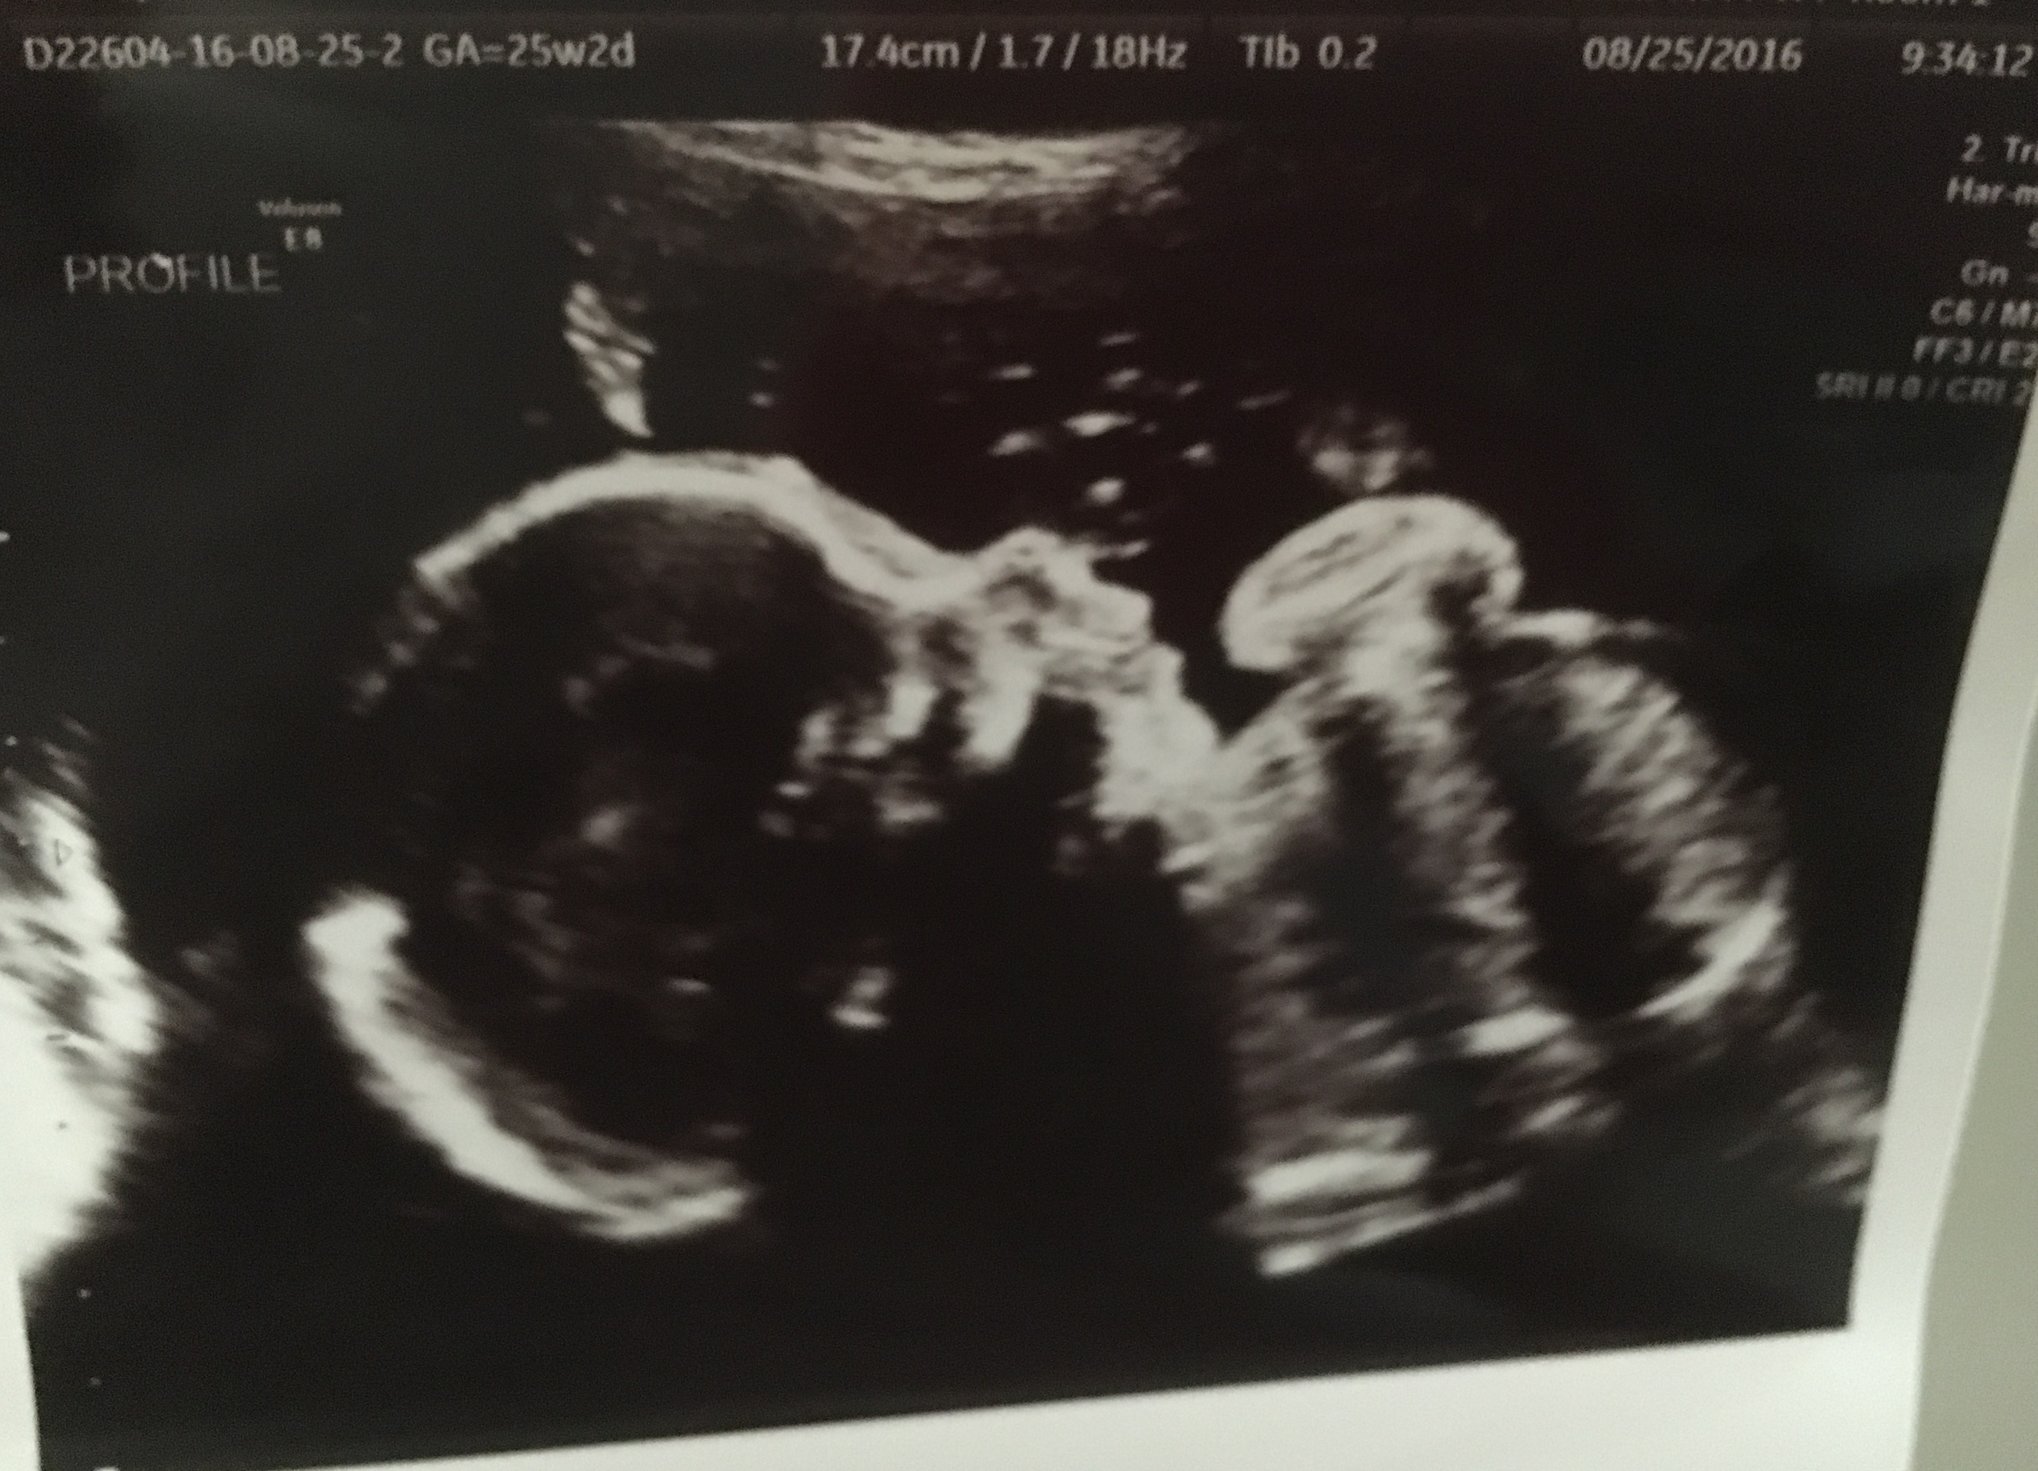

• Hey girls! 25 weeks this week. I have a MFM appt on Thursday for a growth scan. Vacation was nice, but back to reality. Can't believe the 3rd tri & fall is right around the corner... This pregnancy is going by so quickly!